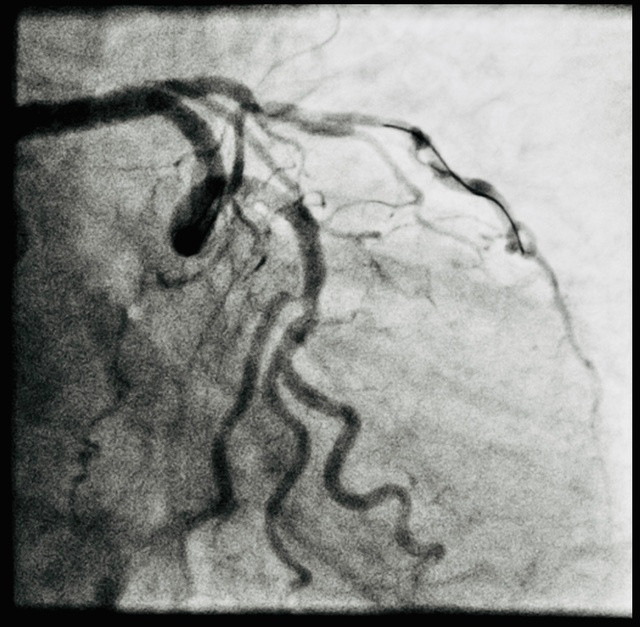

| Hình ảnh mạch vành với tình trạng vôi hóa, tổn thương rất nhiều được can thiệp thành công. Ảnh: THÚY ANH |

Đặc biệt, bệnh nhân bị vôi hóa toàn bộ cả 3 nhánh động mạch vành, tổn thương thân chung động mạch vành trái (đây là vị trí trọng yếu, là gốc của các nhánh động mạch vành bên trái). Động mạch vành là hệ thống mạch máu có chức năng chính là cung cấp máu giàu ô xy cho cơ tim, duy trì hoạt động của quả tim. Với tổn thương ở người bệnh, trước đây chỉ có thể phẫu thuật tim mở.

Trong quá trình tiến hành can thiệp, nhiều kỹ thuật, thao tác khó đã được các bác sĩ thực hiện. Các bác sĩ sử dụng siêu âm trong lòng mạch để hướng dẫn can thiệp chính xác; sử dụng "mẹo" với 2 dây dẫn để trượt stent qua các góc uốn lượn, hoặc cách uốn dây dẫn để "lái" vào những vị trí khó, đảm bảo an toàn người bệnh.

Đặc biệt, trong lần can thiệp này, nhóm tác giả cũng sử dụng kỹ thuật "hybrid" để đặt stent vào nhánh chính lớn. Với nhánh phụ và phần mạch hẹp dài được sử dụng công nghệ bóng phủ thuốc chống tái hẹp nong mạch vành. Các kỹ thuật can thiệp giúp cho người bệnh không phải đặt quá nhiều stent; giảm nguy cơ tái hẹp hoặc tắc lại stent.